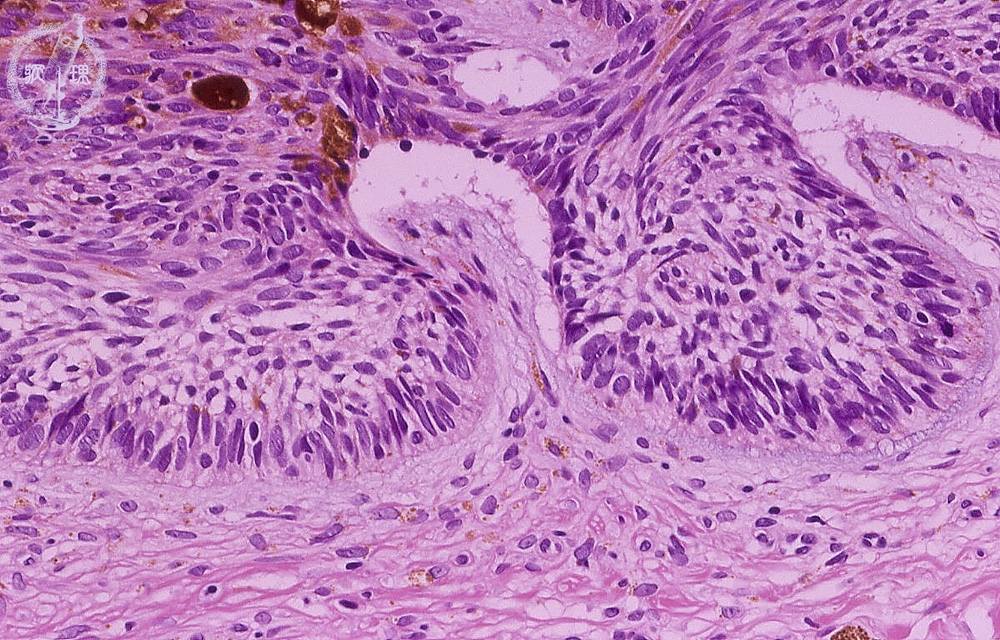

- ★(7)Basal cell carcinoma

The nests of tumor cells show peripheral palisading. Clefts are also present at the edges with the dermis.